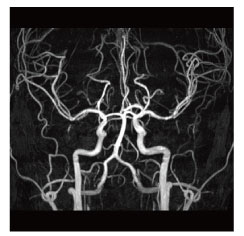

当院のMRI画像集